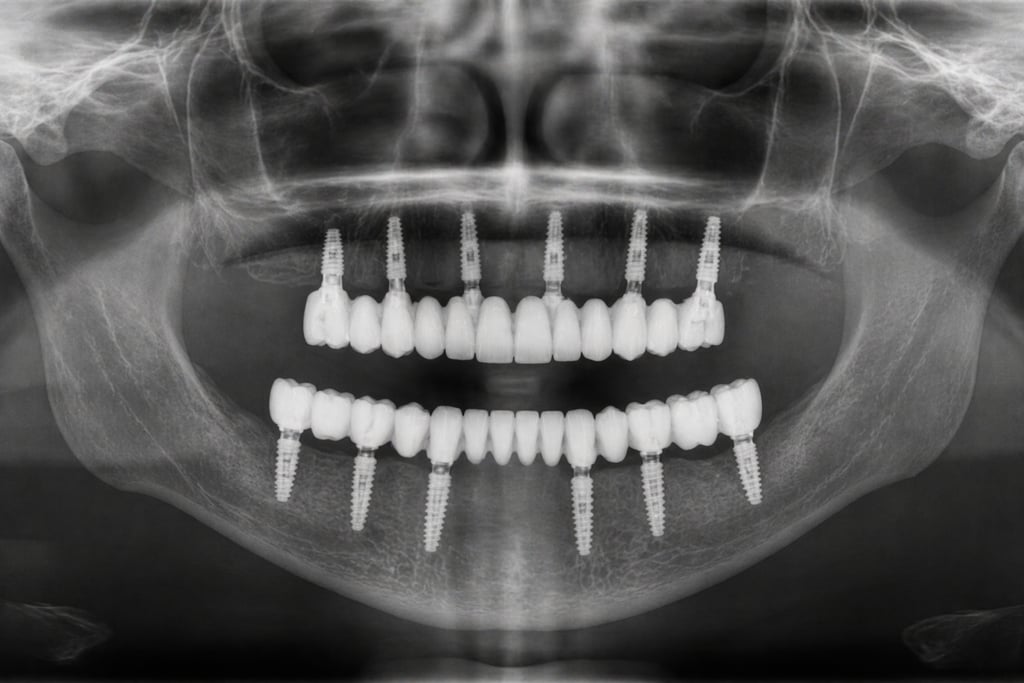

Un implant és una arrel artificial de titani que es col·loca a l'os per substituir la dent perduda. Sobre aquest implant es col·loca una corona que imita perfectament una dent natural.

Rehabilitacions completes (arcades senceres).

Estudi i diagnòstic digital: TAC dental + planificació

Col·locació de l'implant: cirurgia mínimament invasiva

Període d'integració: L'implant s'uneix a l'os

Col·locació de la pròtesi